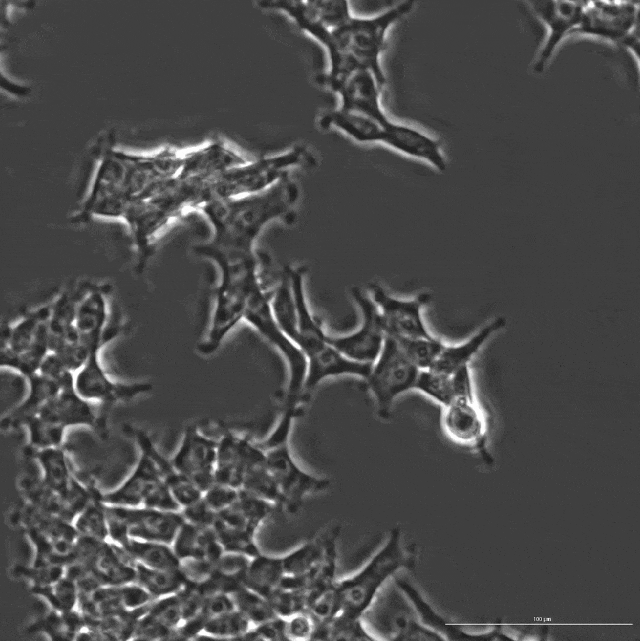

▲ 由 OpenCRISPR-1 编辑的人类细胞延时摄影